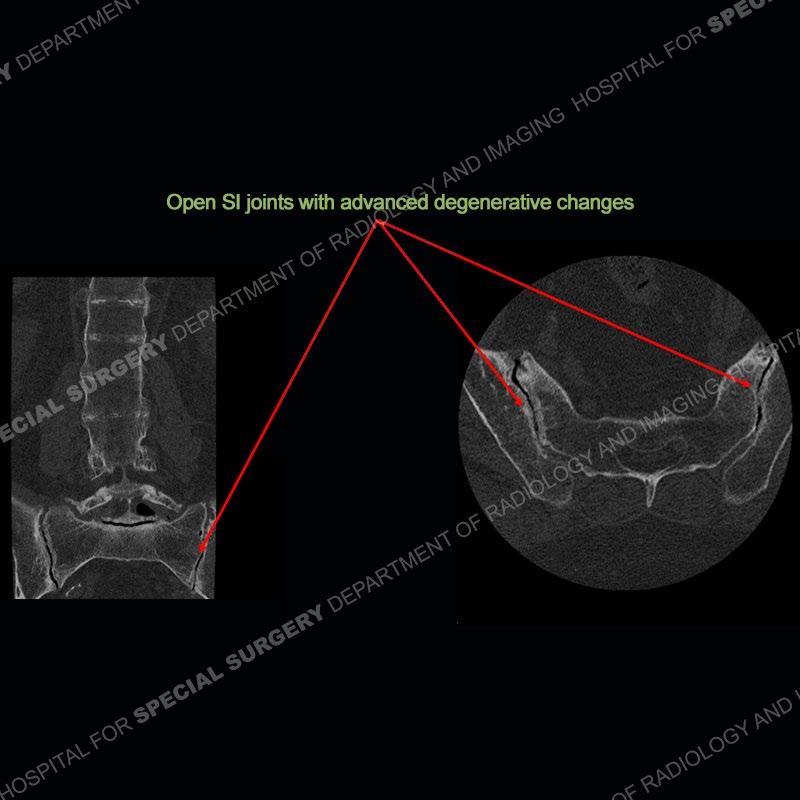

There is severe degenerative change of the left hip. The lumbar and thoracic spine show calcification of the intervertebral discs, loss of disc space, and bulky bony bridging across the disc spaces. Of important note is that the sacroiliac joints are open. They show advanced degenerative changes but not findings of an inflammatory arthritis. Bilateral knee arthroplasties are present and there are severe degenerative changes of both glenohumeral joints.

In comparison to ankylosing spondylitis (AS) where there are thin syndesmophytes of the outer annulus, this bony bridging tends to be bigger and bulkier. In addition, at this stage of AS the sacroiliac joints would be fused, but in ochronosis as seen here, the SI joints are open although with severe degenerative changes. No erosions are present of the SI joints, just advanced degenerative changes. This patient was treated with a left total hip arthroplasty and the black deposition of oxidized homogentistic acid of the cartilage is well shown.